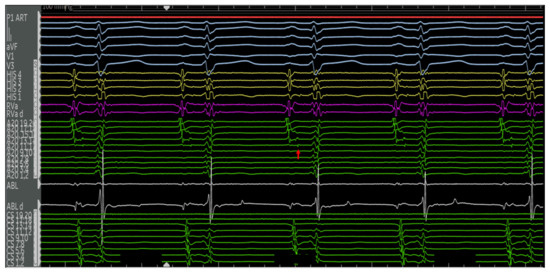

4.2.1. Cases

4.2.2. Case 1